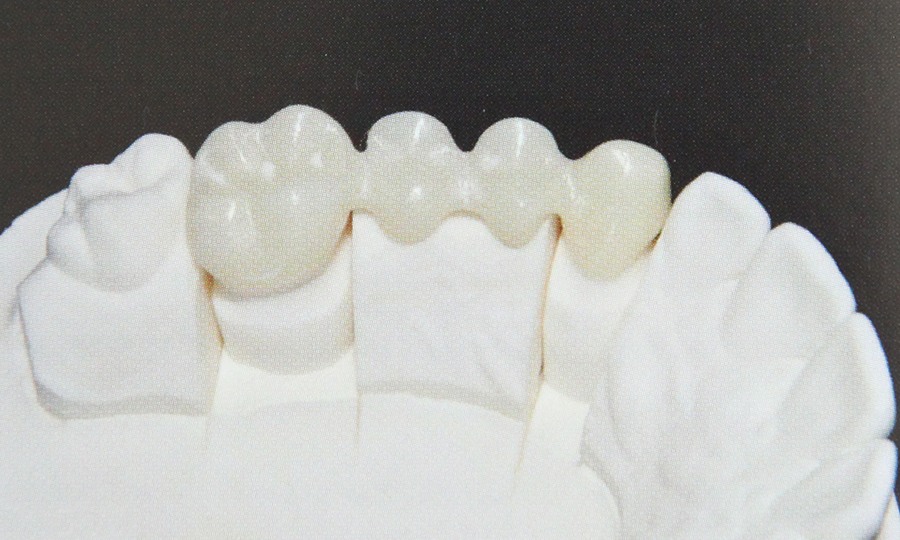

Presupune refacerea structurii dintelui utilizand lucrari protetice atunci cand caria dentara a afectat dintele intr-o masura prea mare pentru a putea fi remediat prin intermediul unei plombe. Daca dintele nu mai poate fi salvat si este extras spatiul lipsa poate fi completat fie printr-o lucrare protetica fie cu ajutorul unui implant. Daca pacientul pierde un numar mai mare de dinti se confectioneaza o proteza dentara.

Pentu ca folosim materiale de cea mai buna calitate pentru ca avem o colaborare stransa cu tehnicienii dentari si pentru ca acordam o atentie deosebita dorintelor pacientilor obtinem lucrari protetice care exceleaza prin estetica si functionalitate. Protetica inseamna refacere dentara prin lucrari protetice diverse.

Aceste lucrari pot fi:  - lucrari metalo- ceramice

- ceramica pe zirconiu

- ceramica integrala